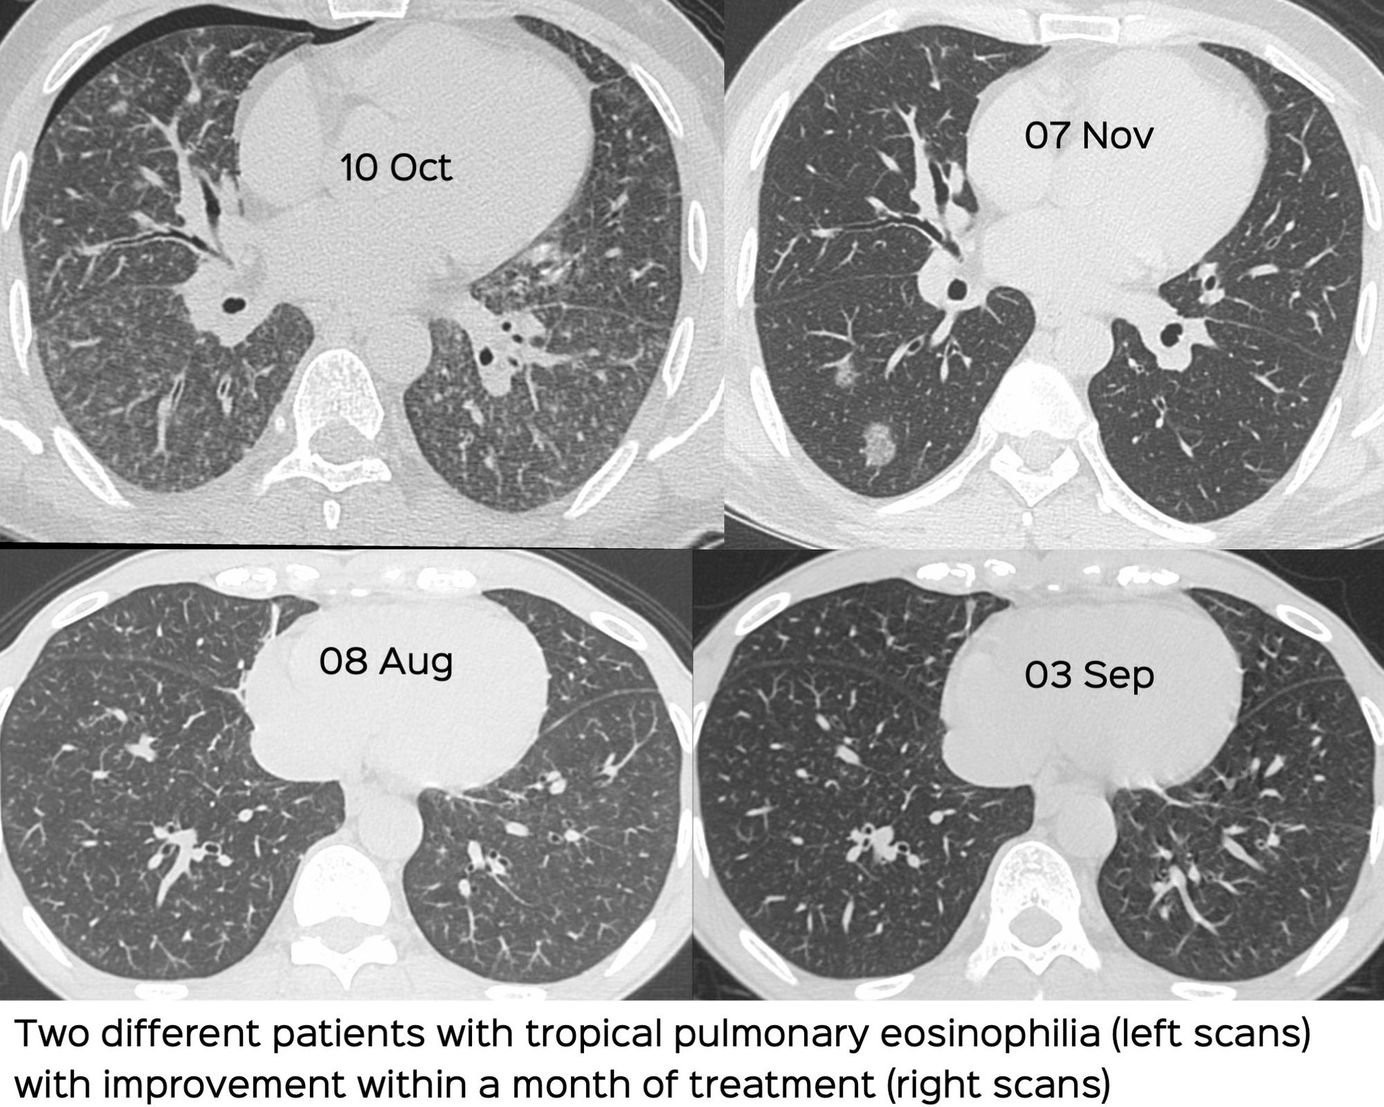

Case 12: Tropical Pulmonary Eosinophilia Members Public

How to suspect tropical pulmonary eosinophilia in acute/subacute settings with diffuse lung disease, especially ill-defined bronchocentric nodules.

Bhavin Jankharia

Interstitial Lung Disease